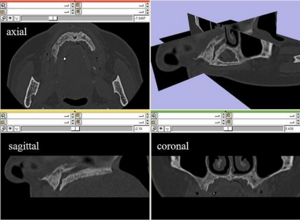

MRI with labeled structures from atlas registered to the CBCT. Registration was carried out with the open source imaging tool 3D Slicer, Version 4.4.0. |